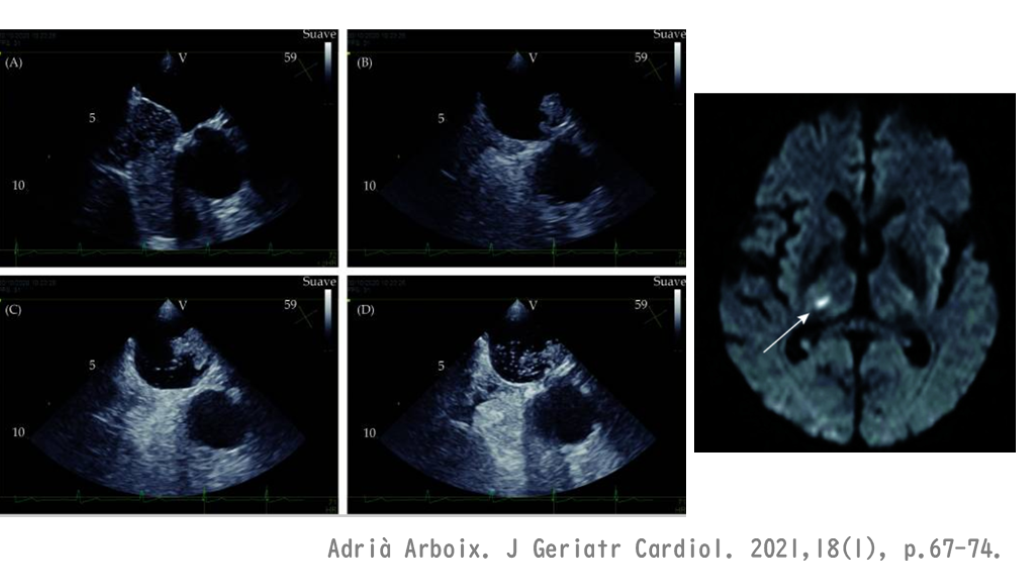

心原性脳塞栓症 心臓が原因の脳梗塞について 最もコモンなのは心房細動による。 ただし、色々な塞栓を起こしうる背景を知っておく。

これは最も発症を防ぐべき、重要な病型。 一言で心原性脳塞栓症を説明するなら、「心臓の中に血栓ができて、その血栓が脳の血管に詰まるタイプの脳梗塞」と言える。 心腔内にできる血栓は大きく、塞栓症を起こした場合、虚血による障害範囲は大きなものになる。 心原性脳塞栓症 簡単な心原性脳塞栓症の理解としては、 「心臓が悪い人に起こる脳梗塞」と 言ってもよい。

心原性の要点:心房細動・心原性脳塞栓症について 心房細動という不整脈が脳梗塞発症の原因となる。 心房細動があると、心腔内に血流のよどみができる。そしてこの血流のよどみが血栓形成の原因になる。この結果できる血栓は動脈血栓よりも巨大な血栓となる。この心腔内の大きな血栓が脳血管にとんで詰まると、脳梗塞を発症する。そして虚血の範囲は広範に及ぶ。 一方、心腔内血栓の形成は必ずしも心房細動の存在が必須ではなく、低心機能状態でも心腔内血栓ができる原因になりうる。

Adrià Arboix. J Geriatr Cardiol. 2021,18(1), p.67-74.